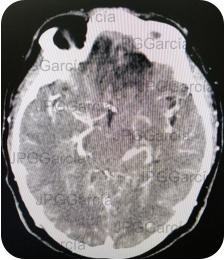

Resonancia magnética de cráneo en secuencias T1 y T2 que muestran una lesión ocupante de espacio de localización fronto temporal izquierda que ejerce efecto de masa aunado a edema perilesional